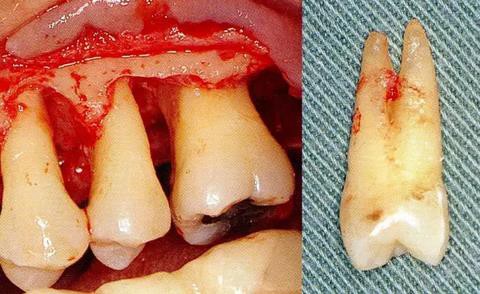

▼圖6-4 下頜第二后磨牙的融合根。在根尖的組合部的產(chǎn)生了附著喪失,導(dǎo)致急速惡化。

[第一前磨牙的根分叉部病變]

▼圖6-5 上頜磨牙部的骨組織缺失。由于左側(cè)第一前磨牙遠(yuǎn)中部的垂直骨組織缺失,導(dǎo)致拔牙。這顆第一前磨牙多數(shù)情況下都是2根分叉,根干很長。所以,這種狀態(tài)下露出根分叉部的話,就不得不進行拔牙。